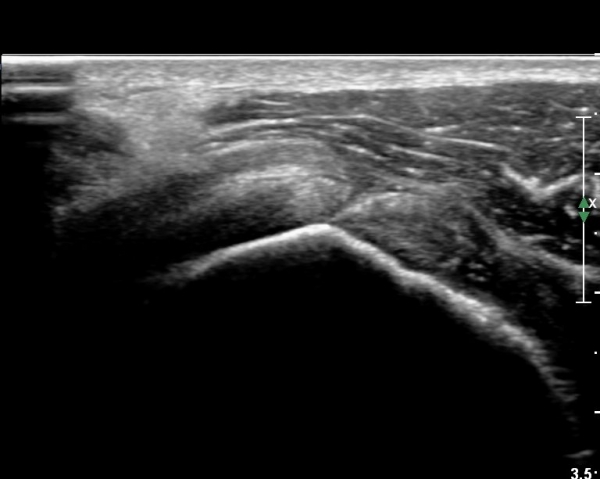

ÆÈÀ» ¿ÜȸÀüÇϸ鼭 °üÂûÇÏ´Ï °ß°©ÇÏ±Ù°Ç ÆÄ¿­ÀÌ ¶Ñ·ÈÇÔ(»çÁø 2, 3).